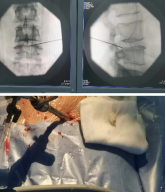

脊柱内镜及微创诊疗技术